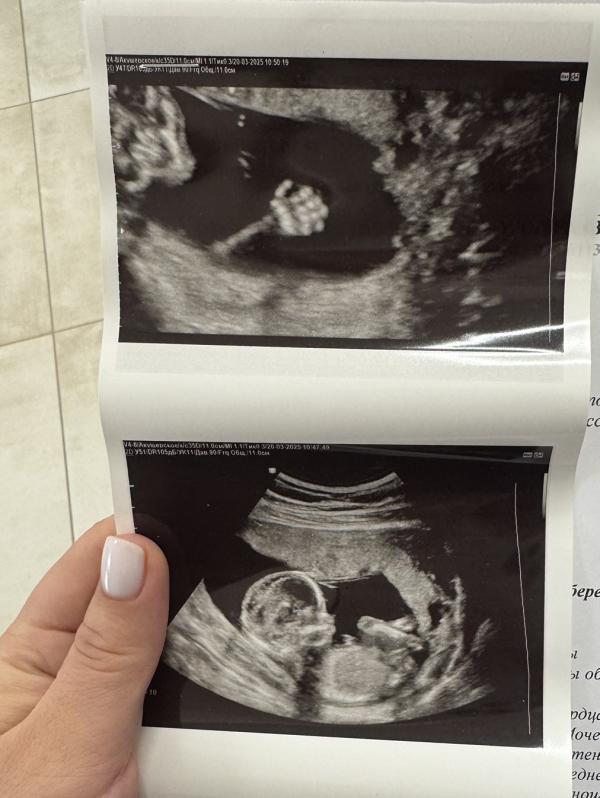

Мы с мужем впервые ходили вместе на узи. Так трогательно🥹Ему было так интересно, вышел из кабинета под впечатлением. Малыш активничал, но закрыл пах руками и ногами, как назло 🤣 Не захотел, чтоб мы узнали, кто же он! Но самое главное, что здоровый и активно развивается🥹

Пупс)) первые фоточки )))